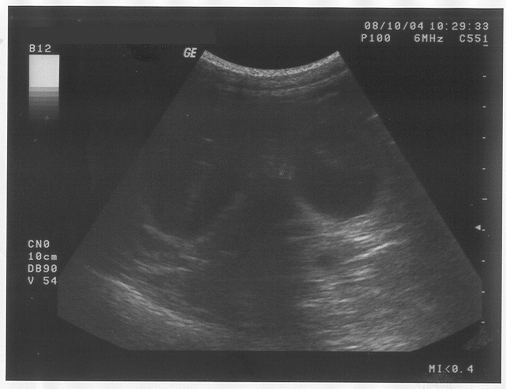

Heute waren wir noch mal bei dem netten Mann, der mich schon untersucht hatte, bevor die ganze Geschichte losging und der auch in der letzten Woche festgestellt hatte, dass ich tatsächlich wieder Babies bekommen werde.

Weil er sich letzten Freitag noch nicht genau festlegen wollte, hatte er angeboten, dass wir heute wiederkommen dürfen.

Er hat mir noch mal diesen Glibberkram auf den Bauch geschmiert und dann haben alle ganz fasziniert auf eine Art Fernseher geschaut. Da kam aber weder "Herrchen gesucht" noch Werbung. Eigentlich hab ich da gar nichts erkennen können.

Nur der Mann und Frauchen und Brigitte, die haben sich gefreut und gemeint, dass es wohl wieder mindestens 6 Babies geben wird. Vielleicht sogar mehr. Ich hab euch die Bilder mal mitgebracht - vielleicht könnt ihr ja was entdecken. Für mich sieht das eher aus wie Seifenblasen.